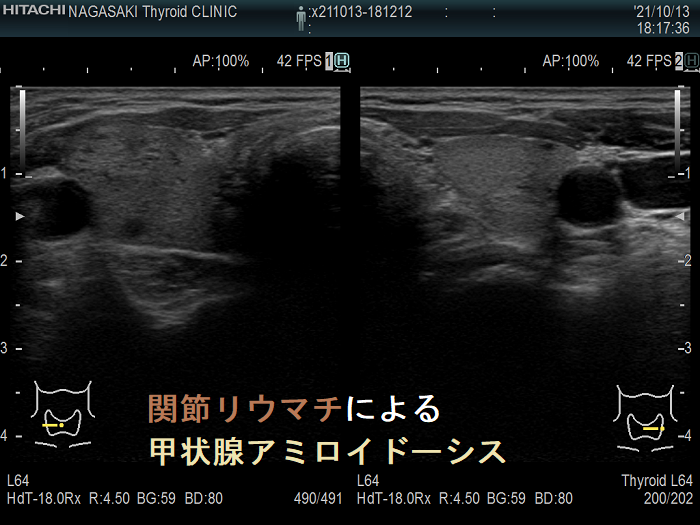

- AAアミロイドーシス:関節リウマチに続発[慢性炎症時, 肝臓から産出される急性期蛋白の血清アミロイドA(SAA)の代謝産物アミロイドA], 家族性地中海熱(周期的に起こる発熱・関節炎・胸膜炎・腹膜炎)でも起こります。

甲状腺アミロイドーシス(関節リウマチ)母娘